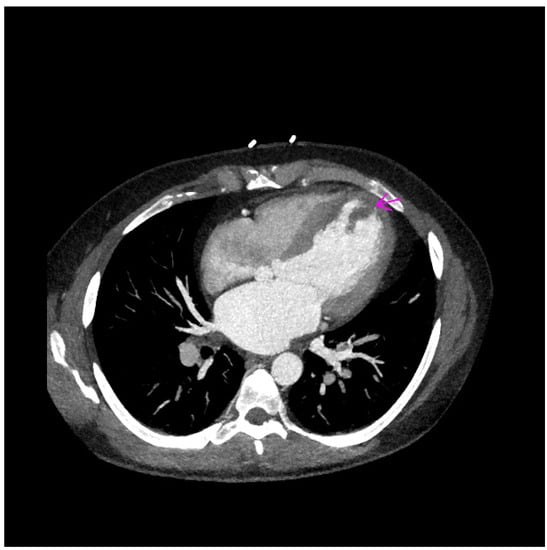

2. Case Report